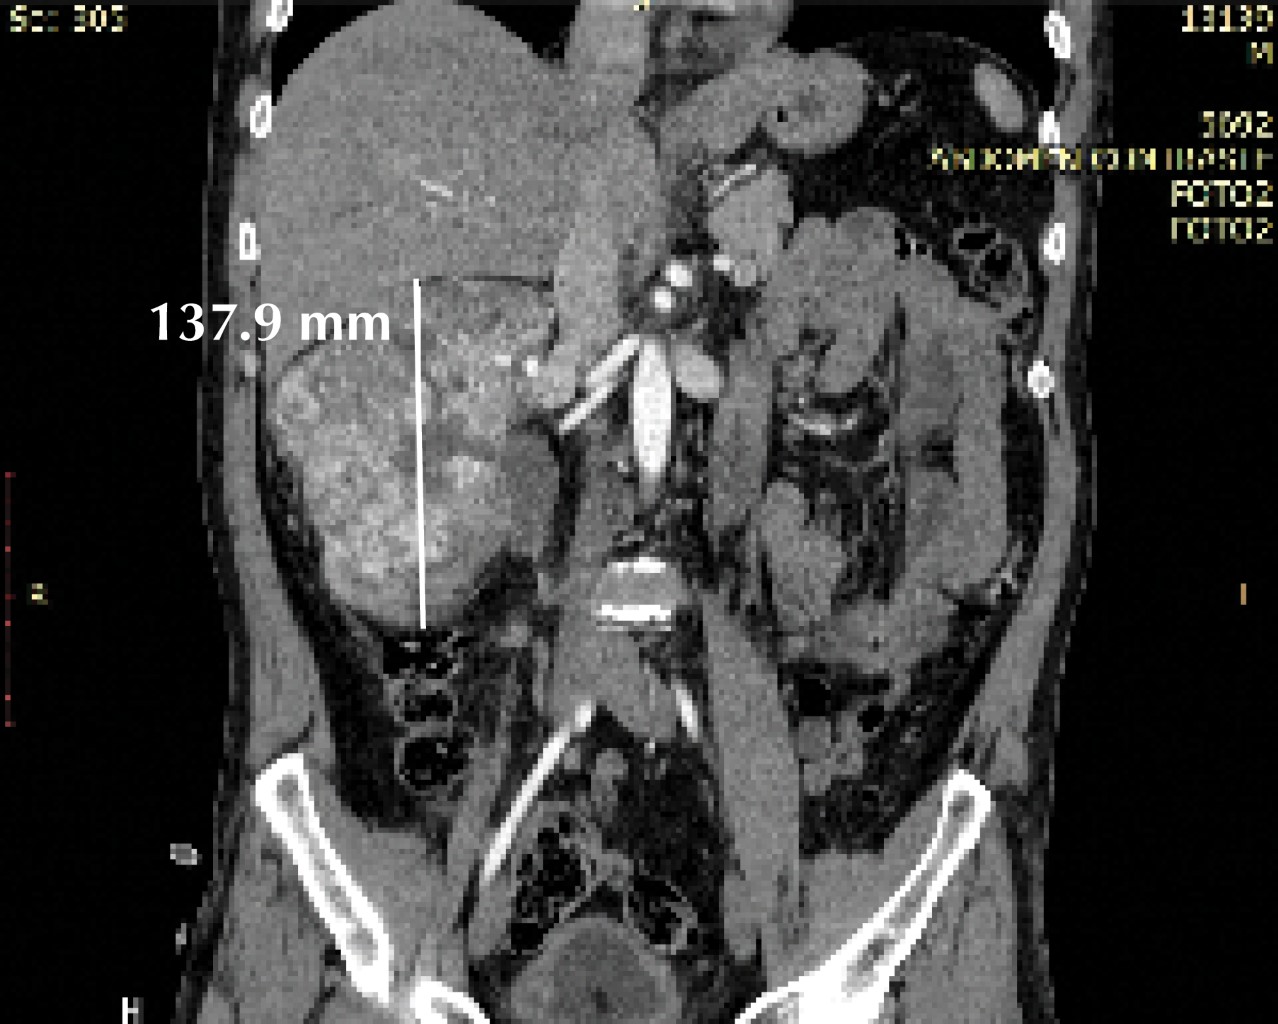

Figure 1